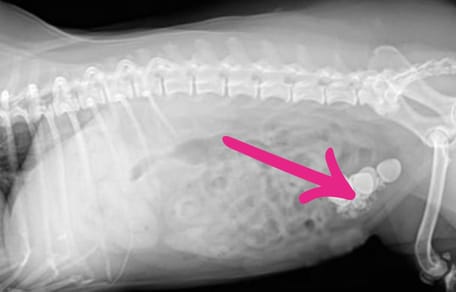

Los veterinarios vieron la cuchara en el interior del perro gracias a una radiografía. Actuaron rápido: pusieron anestesia al animal y sacaron el cubierto de su estómago. Según parece, era la primera vez que veían algo así...